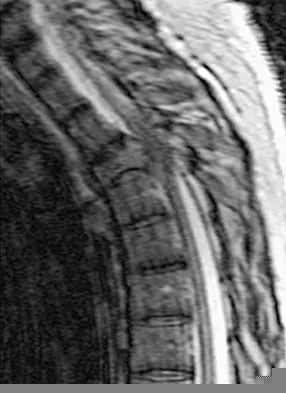

Figures 25a and 25b show the radiograph and MRI scan of a 48-year-old man who reports increasing unsteadiness in his gait and hand clumsiness. Examination reveals a positive Hoffmann's reflex bilaterally, positive clonus, and a spastic gait. Management should consist of